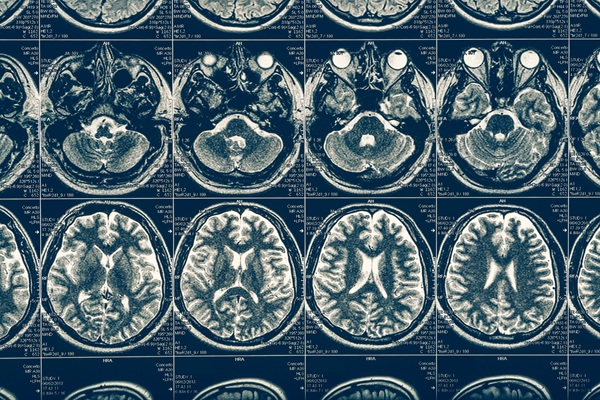

Appointments after hydrocephalus treatment help confirm that pressure stays controlled and symptoms stay stable. The pediatric neurosurgery team may recommend imaging or scheduled checks based on the child's diagnosis and the specific procedure. These visits also allow parents to ask questions about any changes in sleep, appetite, activity, and behavior. Overall, consistent follow-up builds long-term confidence and reduces the risk that small issues will grow into urgent problems.

For many children, hydrocephalus treatment involves either a shunt system or an endoscopic third ventriculostomy (ETV), depending on the cause and anatomy. As per the Mayo Clinic, a shunt uses a flexible tube system to drain excess cerebrospinal fluid to another area of the body, often the abdomen, to reduce pressure. In select cases, an ETV creates an internal pathway for fluid flow, reducing reliance on implanted hardware. The pediatric neurosurgeon will recommend the most effective approach that matches each child's condition and safety needs.